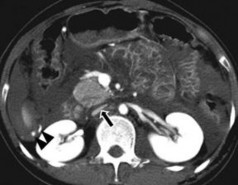

Hình 1.14: CTG độ I. Rách nhu mô: đường vỡ sâu < 1cm (mũi tên).

Nguồn: Shanmuganathan K, Mirvis SE [21].

Hình 1.15: CTG độ II. Rách nhu mô sâu 1-3 cm, dài < 10 cm (mũi tên).

Hình 1.16: CTG độ II. Tụ máu dưới bao gan 10–50% diện tích bề mặt.